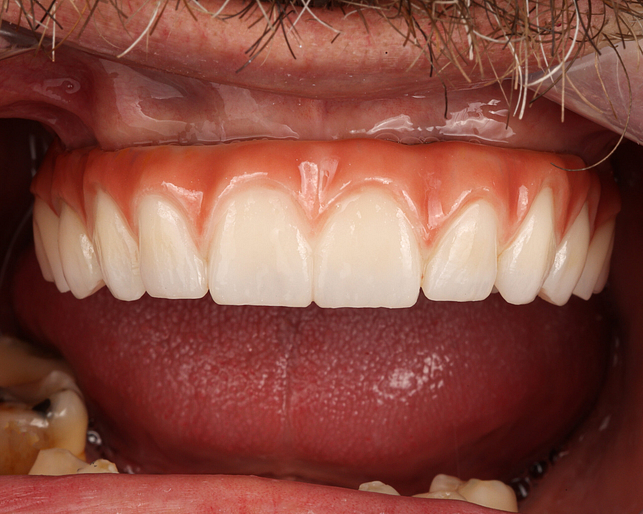

After